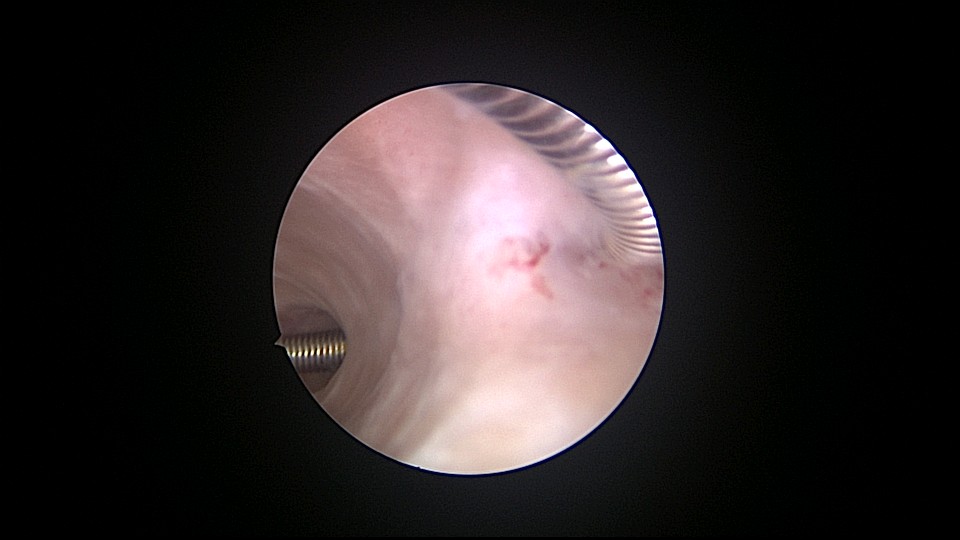

患者56岁,G4P1,顺产1次。1990、1991、1992年三次安环,均自然脱落,1993年第4次安环至今,共31年。现绝经4年,外院取环失败。患者阴道、宫颈、子宫萎缩,宫颈外口无法夹持,探针、中弯钳均无法打开宫颈外口,一筹莫展多时。最后用缝线缝住宫颈11点位及1点位,牵拉宫颈,尖刀片十字切开宫颈外口,B超监护下宫腔镜艰难进入宫颈管,见宫颈管封闭粘连,宫颈内口左侧粘膜下肌瘤遮挡视野。多次努力,镜子成功进入宫腔,见O型环两侧与子宫肌壁嵌顿,异物钳牵拉几次失败,用取环钩钩取,多次尝试终于成功钩住环,牵拉到宫颈外口,用中弯钳取出节育环,环变形,宫壁见节育环割裂痕迹,宫腔少许积血,无其他异常。